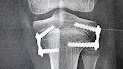

We found out recently that Cassandra needs reconstructive surgery on her knee to remove a plate that was put in two years ago. The plate, and the screws in it, are bent upward/downward at an extreme degree. The upper screw is now going through her good growth plate and into the back of her knee cap causing her constant pain. Instead of removing the screws next year we now have a month to get them removed or it will risk permanent damage to her knee and bone.

** I added a picture of one of her last x-rays to show what has happened with the screws. I also added another picture of what the concept is should do.**